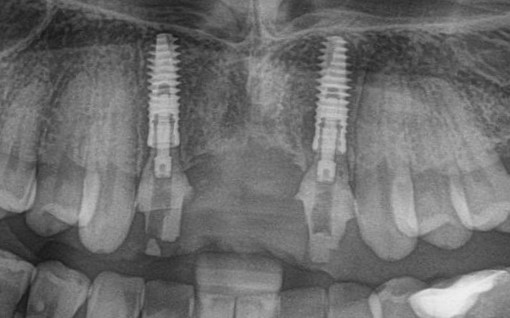

Таким образом, мы устанавливаем оба имплантата:

Наш физиодиспенсер позволяет измерять крутящий момент при установке — у нас получилось среднее значение около 20 Нсм. Этого достаточно для немедленного протезирования.

Но прежде, чем мы к нему перейдём, еще раз проверим положение имплантатов:

Теперь нужно сделать контрольные снимки, чтобы убедиться, что абатменты сели на платформу имплантата. В нашем случае, абатменты пришлось подточить:

Мы делаем еще один контрольный снимок, чтобы убедиться, в правильной посадке протеза: